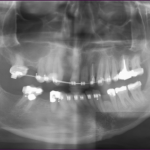

The bone used in a sinus lift may come from your own body (autogenous bone), from a cadaver (allogeneic bone) or from cow bone (xenograft). You will need X-rays taken before your sinus lift so the dentist can study the anatomy of your jaw and sinus. You also may need a special type of computed tomography (CBCT) scan. This scan will allow the dentist to accurately measure the height and width of your existing bone and to evaluate the health of your sinus.

A sinus lift is done when there is not enough bone height in the upper jaw, or the sinuses are too close to the jaw, for dental implants to be placed. There are several reasons for this:

• Many people who have lost teeth in their upper jaw — particularly the back teeth, or molars — do not have enough bone for implants to be placed. Because of the anatomy of the skull, the back of the upper jaw has less bone than the lower jaw.

• The maxillary sinus may be too close to the upper jaw for implants to be placed. The shape and the size of this sinus varies from person to person. The sinus also can get larger as you age.